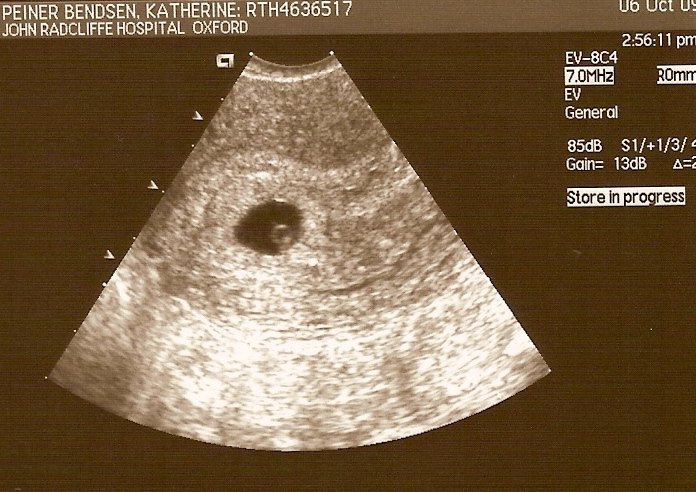

Jeg skulle til undersøgelses-scanning på sygehuset for at blive undersøgt for PCO. Da jeg var til scanning, var jeg gået 6 uger over tid og tænkte, at min menstruation blot var forsinket igen, som den altid var og havde været det igennem det sidste 1 1/2 år.

Sygeplejersken begyndte scanningen af min livmoder og æggestokke. Efter et par minutter vendte hun skærmen mod mig. På skærmen sås en lille rund cirkel, som lå i min livmoder. ”Sådan en ses normalt kun i forbindelse med graviditet”, sagde hun

Herefter foretog hun en indvendig scanning, som bekræftede, at jeg var gravid i ca. 6. uge. Det var helt tydeligt at der var liv i min mave. Et lille hjerte, som bankede med al hast, kunne tydeligt ses

, da jeg under køreturen hjem viste ham scannings billedet af vores kommende barn. Jeg selv var ved at køre af vejen, da jeg forsøgte at forklare hvad som var hvad på billedet